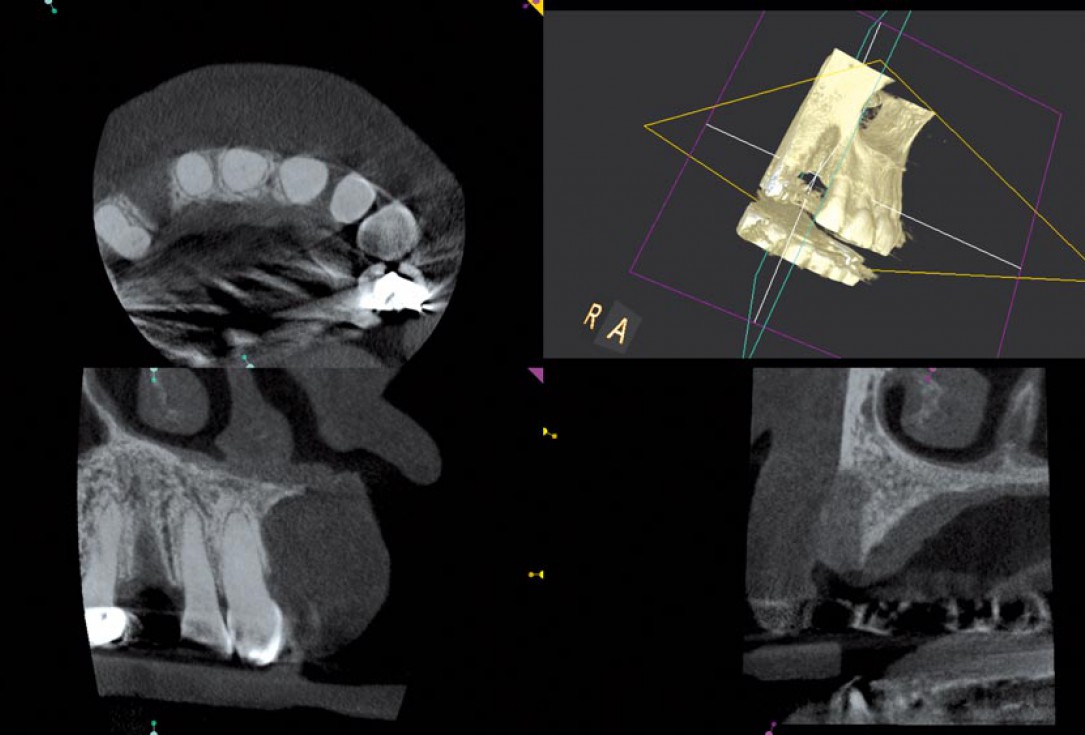

03/12 - Initial CBCT scan

Block augmentation with maxgraft® in the maxilla - PD Dr. Dr. F. Kloss